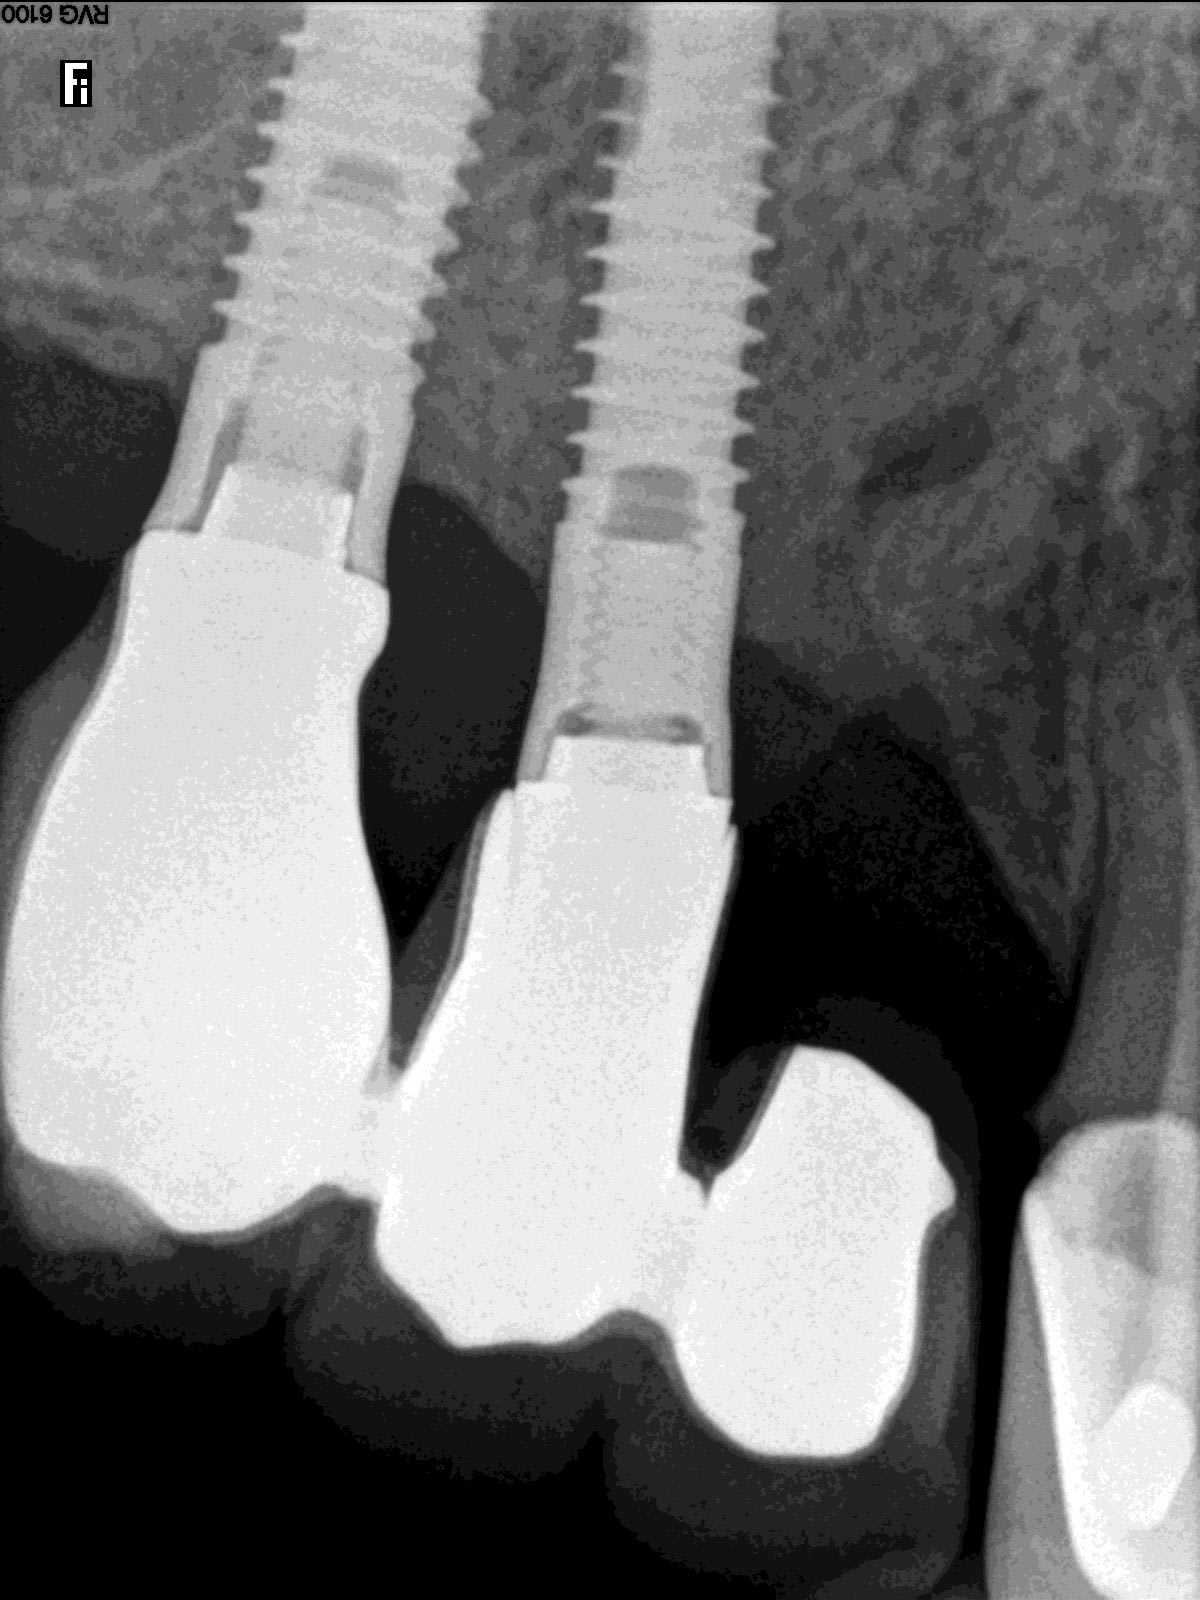

et voila messieurs !

et...heu...tu sais c que c'est comme implant?

parce que si tu veux une identification va falloir faire mieux que des photos merdiques prises au smartphone comme çà!!!

exporte comme il faut tes radios nom de Dieu!!!

Ce sont des Serf... je bosse sur mac et c'est pas évident quand on ne maitrise pas mac pour sortir les radios. J'espère que ça conviendra

serf EVL donc connexion à plat...ce qui veut dire multiunits inutiles si tu n'utilises pas l'hexagone (ce qui est le cas déjà ici si tu étudies bien la rétroalvéolaire)

mais!: l'implant le plus mésial n'est pas dans un axe idéal ce qui veut dire que l'émergence de la vis sera merdique à gérer si tu veux faire de la transvissée...

tu n'as pas d'autre choix que de refaire de la scellée pour ce cas...et petit conseil, utilise des piliers indexés et non pas des piliers sans indexation comme ici...

amha çà c'est dévissé car les piliers n'ont pas étés mis dans la bonne position, ils ont été vissés/serrés de travers...la mastication les a fait revenir dans la bonne position...mais du coup ils ne sont plus serrés...